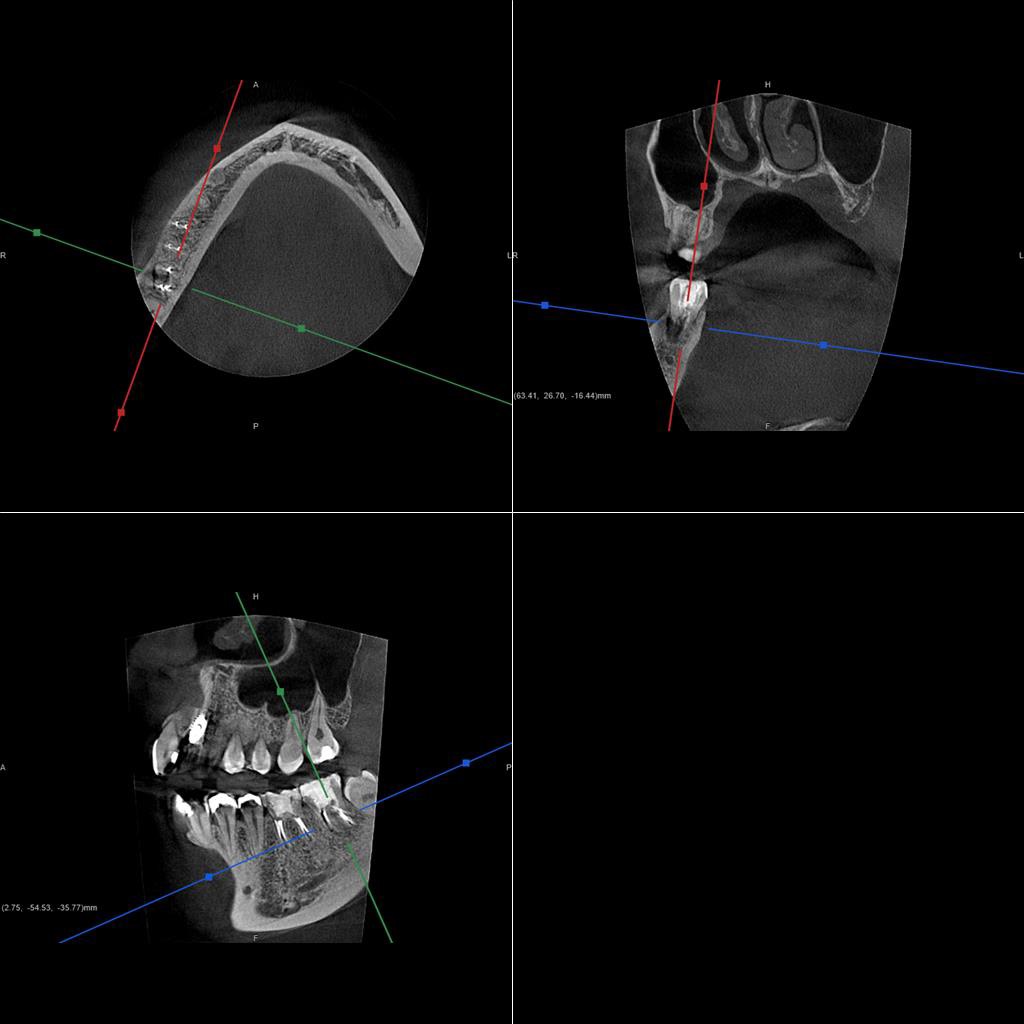

30代、女性、右下に違和感があることを健診中に申され、インプラント治療を行いました。

| 診断結果 | 右下7番歯根破折 |

| 治療内容 | 抜歯即時インプラント |